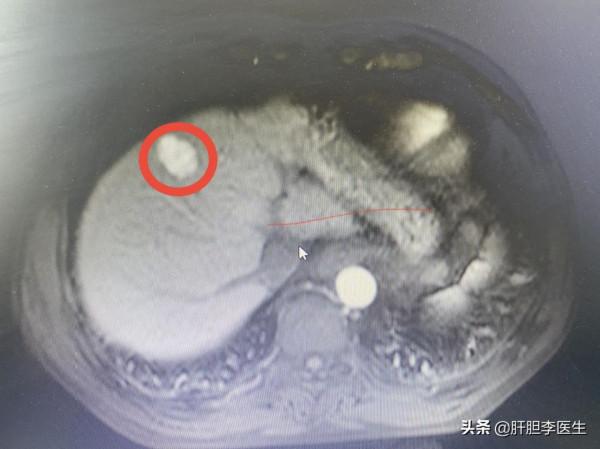

這次到上海來就診,然後就給他複查了一下增強CT,發現肝臟腫瘤有6cm大小,雖然腫瘤比較大,但是仍有手術切除的機會。於是就建議病人進行手術治療,但是病人的回答卻仍然意外:我們不做手術。回答得很乾脆,一點猶豫都沒有,彷彿對手術治療根本不相信,而且很鄙視手術的那種感覺。後來的話更讓我們震驚。

這個病人,兩個月前的時候發現腫瘤2.5釐米大小,然後沒有進行任何治療,這次再複查,腫瘤就變成了6釐米大小,也就是說,兩個月的時間,腫瘤長大了3釐米多。這個速度還是挺快的,也能說明肝癌的惡性程度比較高,生長速度比較快。